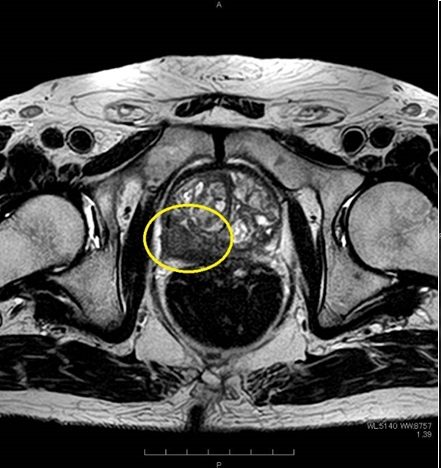

PSAが高値などの前立腺がんを疑う場合は、前立腺のMRI検査を行います。 前立腺MRIは、前立腺がんの診断に大変有用な検査で、前立腺がんの有無だけではなくがんの位置や大きさ、悪性度もある程度予測する事が可能となります。 また、疑わしい場所があった場合に行う前立腺生検の際、こちらの画像を前立腺生検の装置に取り込み、実際の超音波画像と融合する事により正確に前立腺がんと疑われる場所の組織を採取する事が出来ます。(MRI融合前立腺生検)